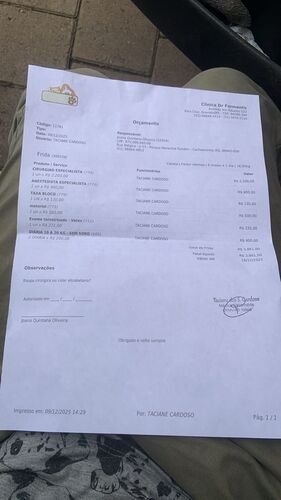

A cirurgia custa R$ 3.900,00, sem contar medicação, soro e outros itens que não entrarão no orçamento.